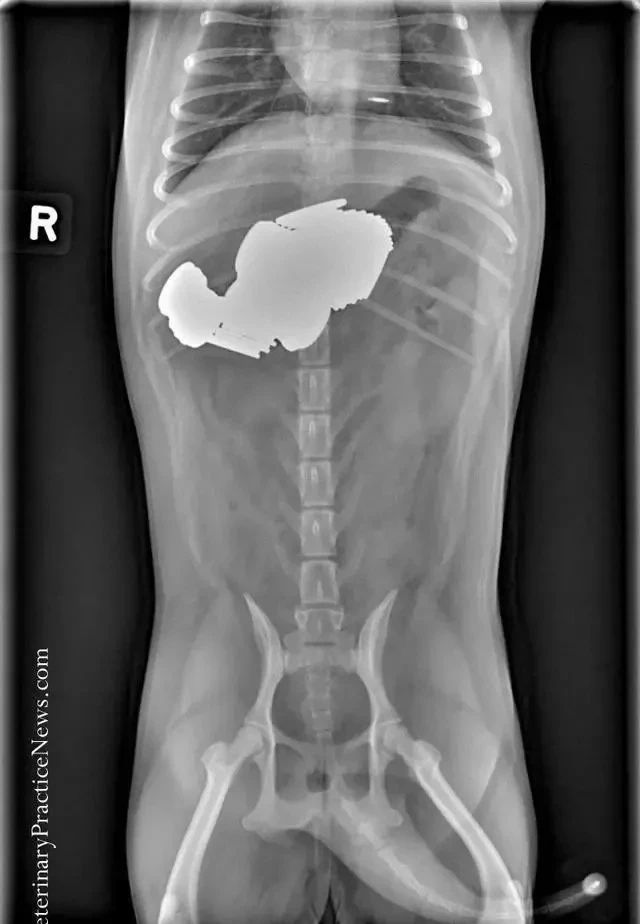

有宠物医院专门PO出了一些X光影像来提醒铲屎官注意狗狗异食行为,看看它们吞下的东西简直让人瞠目结舌。

因为假牙上有食物残渣,所以吞下了主人假牙。